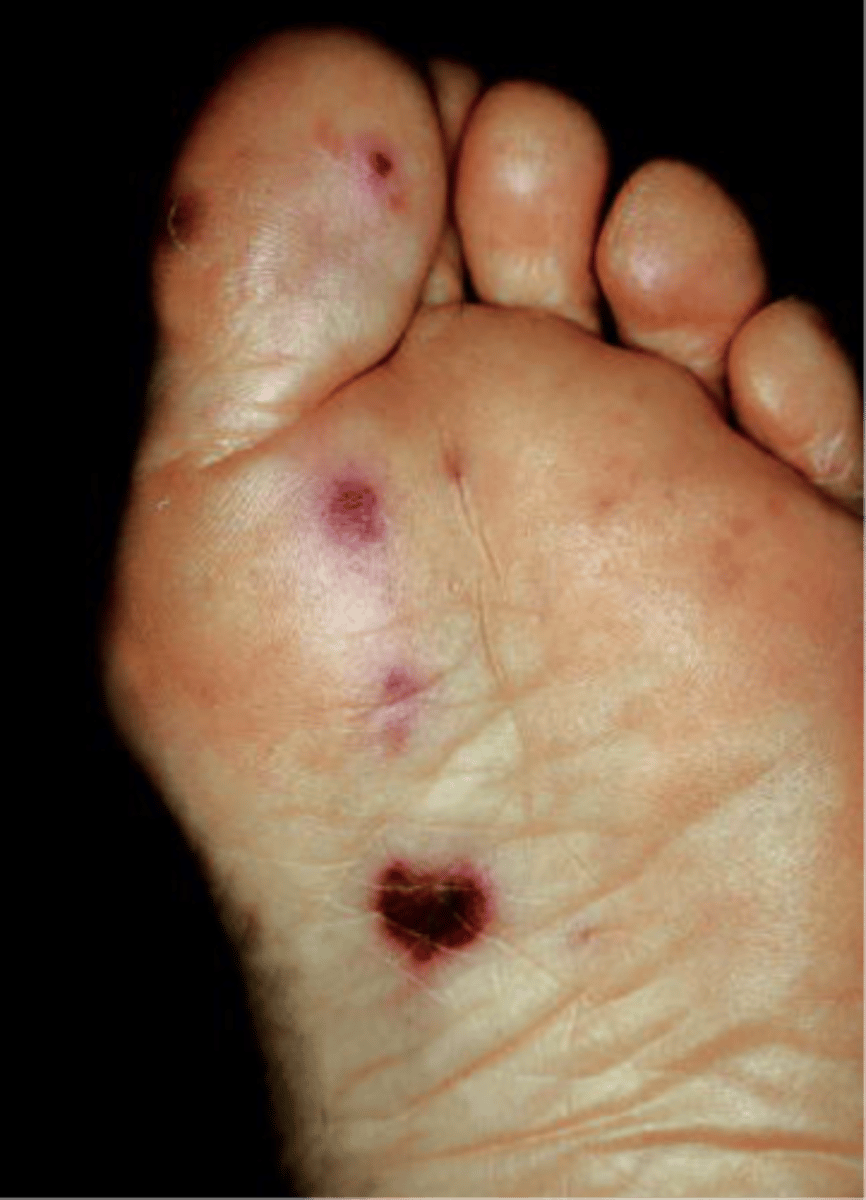

Janeway's lesions

Painless erythematous nodules on palms and soles of feet